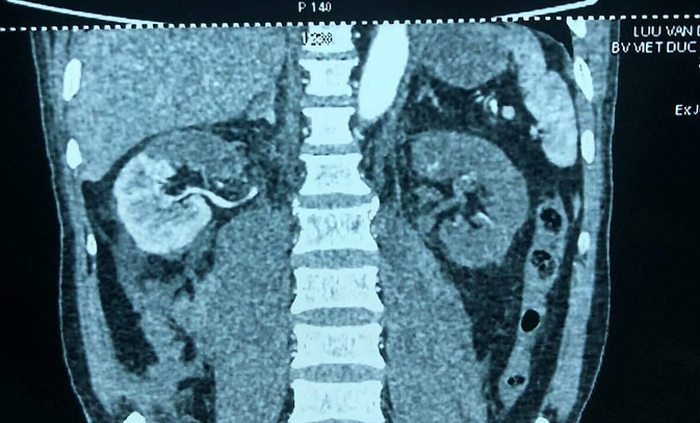

Bệnh nhân gặp nạn chấn thương thận, bác sĩ Bệnh viện Việt Đức cắt quả thận tím đen ra khỏi cơ thể để rửa rồi ghép lại như cũ.